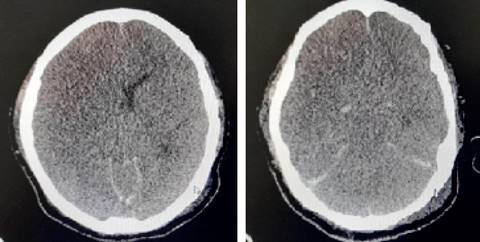

A las 48 horas de su ingreso a UCI, presenta cambios en estado neurológico con pupilas midriáticas de 5 mm sin respuesta a estímulos luminosos, hipotensión arterial que requirió inicio de vasopresor. Se realiza tomografía simple de cráneo que reporta edema cerebral difuso y hemorragia subaracnoidea (Figura 2). Se realiza electroencefalograma que reporta ausencia de actividad cortical cerebral. En el tercer día de su ingreso a la UCI, presenta hipotensión arterial con incremento en las dosis de vasopresor, presentando de manera posterior bradicardia y asistolia, iniciando maniobras de reanimación cardiopulmonar sin retorno a la circulación espontánea.

Otro factor de mal pronóstico en nuestra paciente fue la patología de base; la leucemia promielocítica aguda es diferente de los otros tipos de LMA debido a que el riesgo de complicaciones mortales es mayor.11,12 Esto se debe a que las células leucémicas de la leucemia promielocítica aguda contienen gránulos cargados de proteínas y enzimas que al ser liberadas a la circulación ocasiona consumo de factores de coagulación, lo que unido al descenso del conteo plaquetario puede ocasionar hemorragias graves como hemorragia cerebral y coagulación intravascular diseminada con fenómenos de trombosis.13-15 En nuestra paciente se complicó con la presencia de hemorragia subaracnoidea y edema cerebral que contribuyó al resultado final.